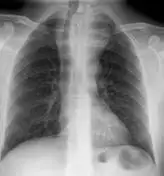

如果肉芽肿破裂,结核菌就会逃入周围组织,甚至进入血液循环。这就是所谓的"血行播散",可以导致全身多器官的结核感染。在X光片上,这种广泛播散的结核病灶呈现出无数细小的点状阴影,如同撒在肺部的粟粒,因此被称为"粟粒性结核"。在抗生素出现之前,粟粒性结核几乎百分之百致命。